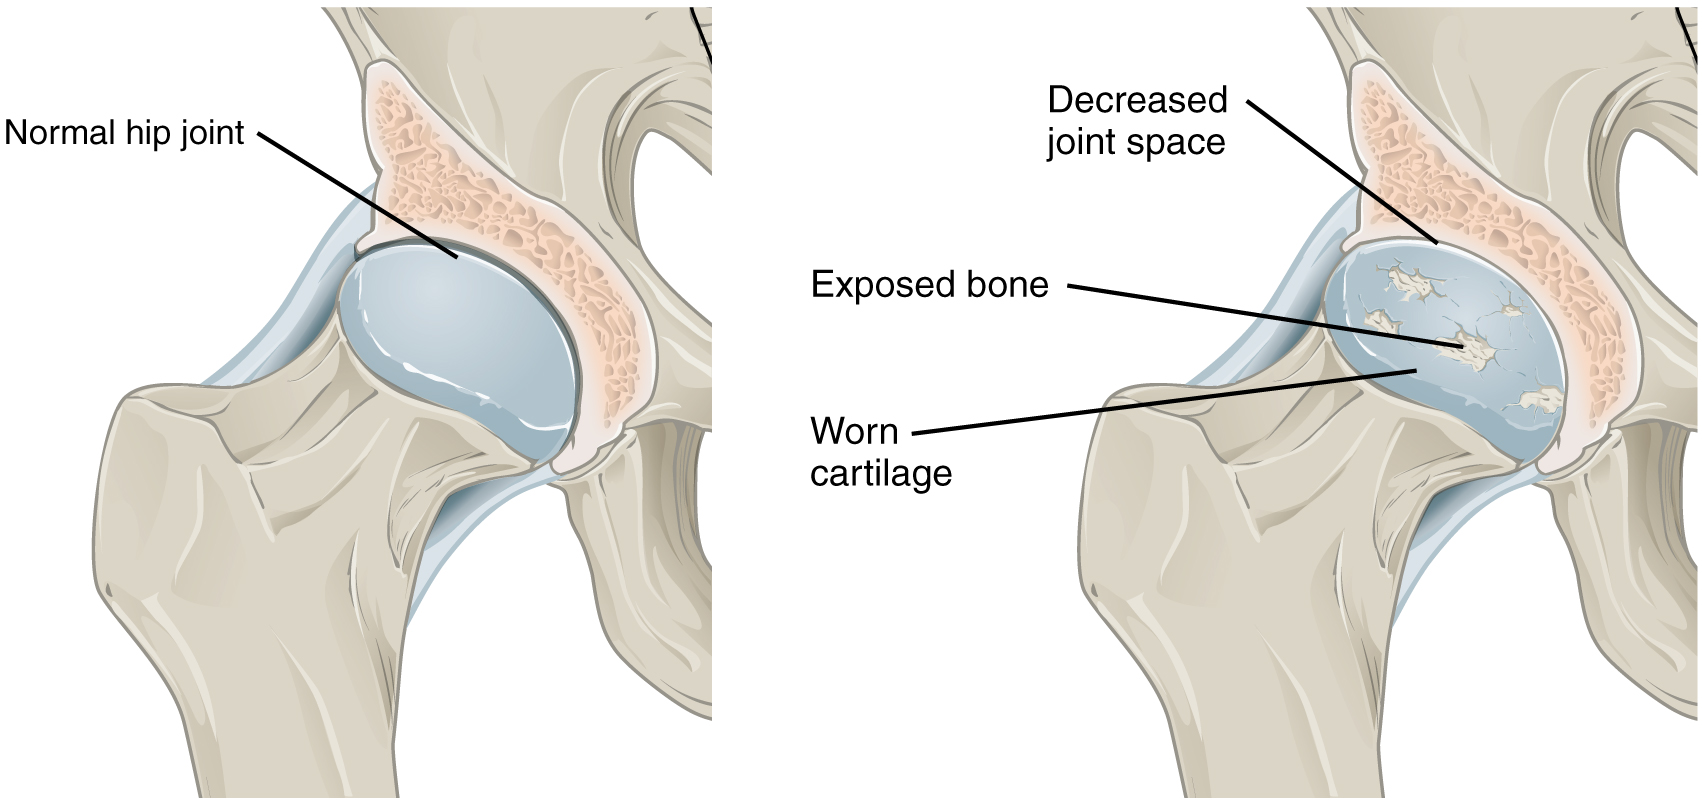

Arthritic changes – Arthritis is related to a condition of painful joints due to inflammation or swelling. A type of arthritis is rheumatoid arthritis, it is an autoimmune disease where the immune system attacks the joints, starting with the lining of joints. Rheumatoid arthritis is heavily related to lung problems, about 80% of arthritic patients have lung-related issues, making it the second leading cause of death with rheumatoid arthritis patients. Rheumatoid arthritis caused lung problems are most commonly extra-articular i.e., outside of the joints and involves pulmonary nodules; damage to the lung airways, pleural effusion and interstitial lung disease. In rheumatoid arthritis associated interstitial lung disease the auto-immune system gets over active and attacks the lungs and causes scarring. With time, the scarring build-up leads to difficulty breathing and reduced lung function.